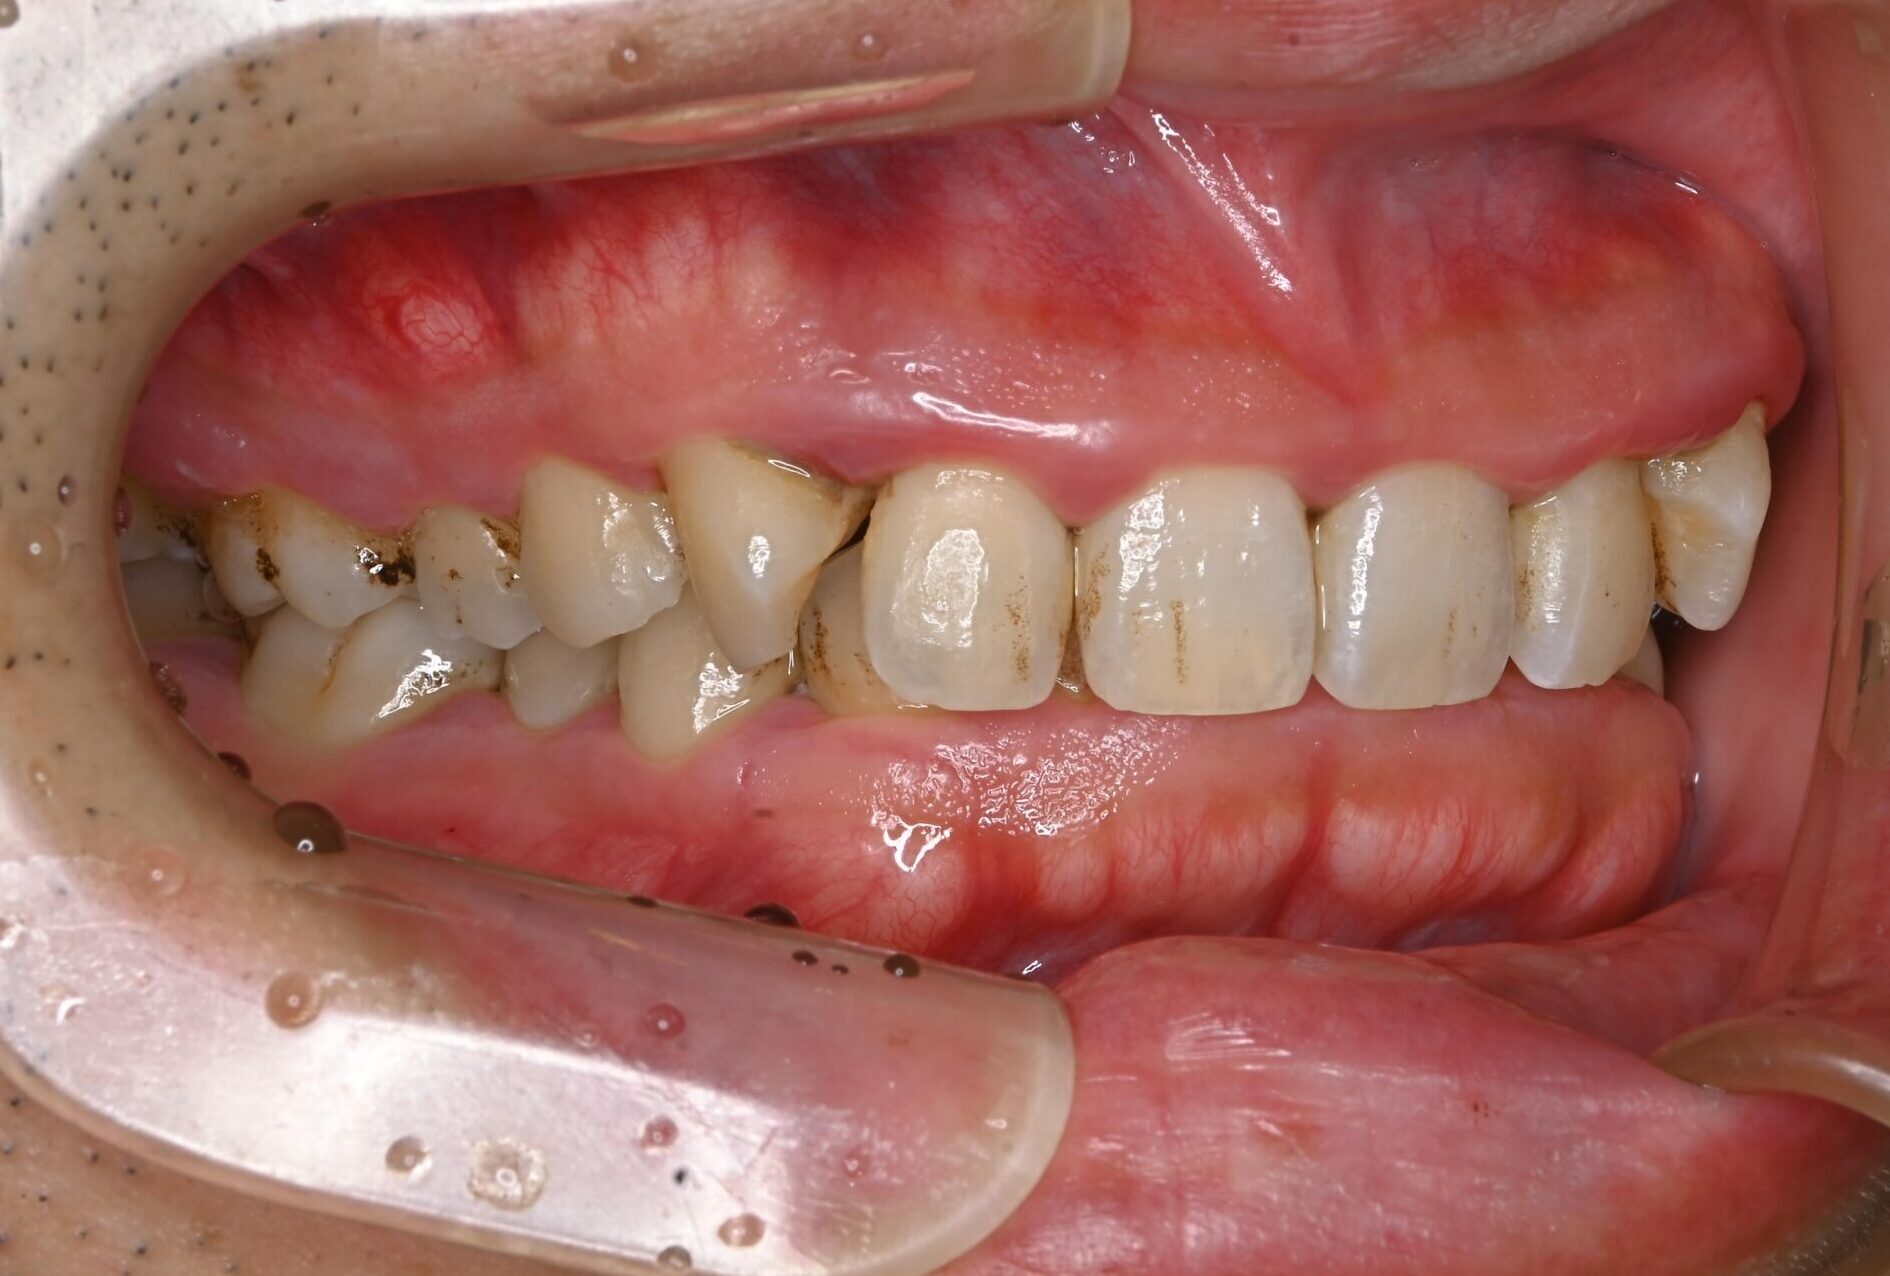

30代・男性

歯茎から出血、歯石除去|中等度に進行した歯周病

症例写真 before

中等度歯周病

歯医者が久しぶりなのでクリーニングをしてほしい、ということで来院されました。

レントゲン撮影、歯周検査などを行なった結果、全体に多くの歯石付着が認められる進行した中等度の歯周病であることが判明しました。ご本人も歯茎から出血することは気になっており、担当歯科衛生士から歯周病について説明を行いました。

今回は歯石の付着が広範囲に渡っており量も多いことから、歯科衛生士による歯周基本治療に加え歯科医師による外科手術も行うことで、徹底的に治療していくことになりました。